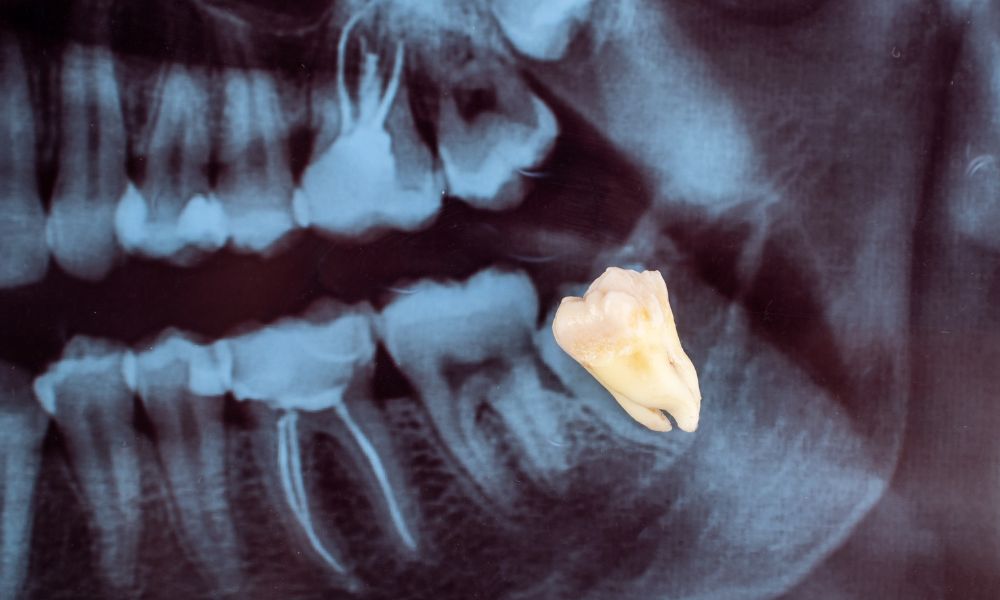

Zuby múdrosti, alebo tzv. „osmičky“, sú najvzdialenejšie stoličky, určené na drvenie jedla.

- Málo miesta v ústnej dutine. Môže sa stať, že v ústach proste na tieto zuby nemáte dosť miesta. Zubár to zistí z röntgenu a môže pristúpiť k extrakcii, aby predišiel problémom.

Extrakcia zubov múdrosti prebieha väčšinou chirurgicky. Zubný chirurg v lokálnej alebo celkovej anestézii rozreže ďasno, aby odhalil zub a kosť.

Následne zub a koreň vyberie a ďasno zašije.